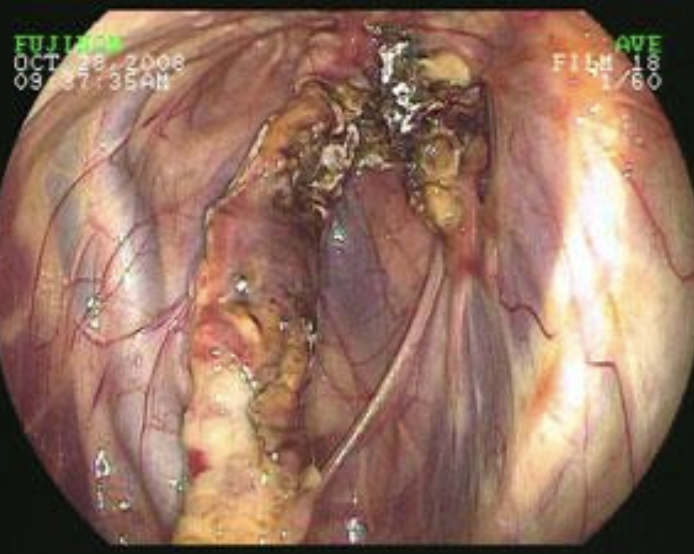

1. endoscopy (visualization of blood in trachea)

2. ultrasound: liver abscess, dilation of CVC